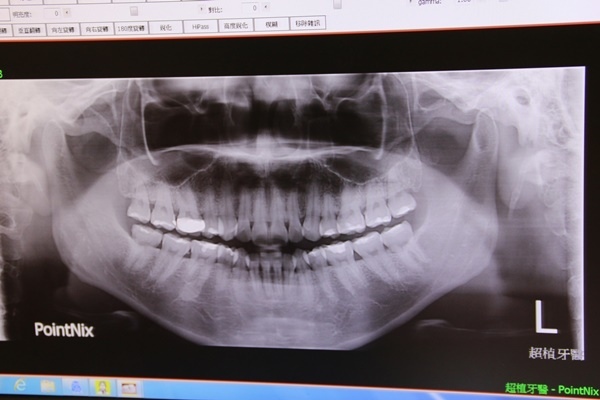

第一次來這邊看牙齒,一定要照一張美美的X光片!讓醫生知道你目前的牙齒狀況~!